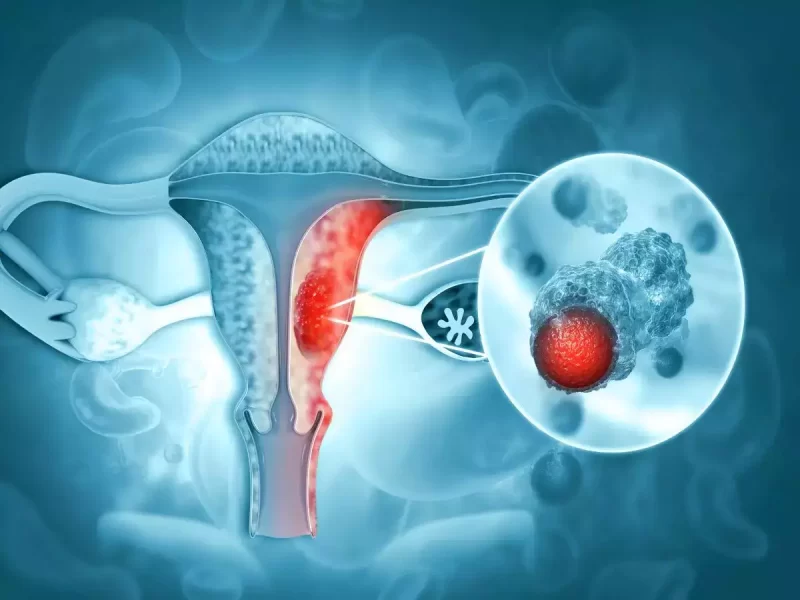

Innovative Oncology Services

Our Services

Oncology Services